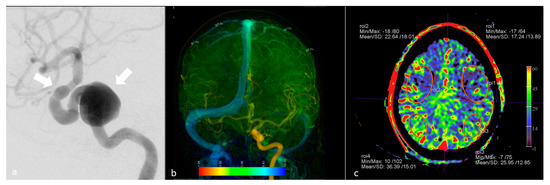

- Yang, M.; Wu, J.; Ma, L.; Pan, L.; Li, J.; Chen, G.; Struffert, T.; Sun, Q.; Beilner, J.; Deuerling-Zheng, Y. The Value of syngo DynaPBV Neuro During Neuro-Interventional Hypotensive Balloon Occlusion Test. Clin. Neuroradiol. 2015, 25, 387–395. [Google Scholar] [CrossRef]

- Ikemura, A.; Yuki, I.; Otani, K.; Ishibashi, T.; Dahmani, C.; Ebara, M.; Abe, Y.; Kajiwara, I.; Watanabe, M.; Murayama, Y. Evaluation of Balloon Test Occlusion Before Therapeutic Carotid Artery Occlusion: Flat Detector Computed Tomography Cerebral Blood Volume Imaging versus Single-Photon Emission Computed Tomography. World Neurosurg. 2019, 133, e522–e528. [Google Scholar] [CrossRef]